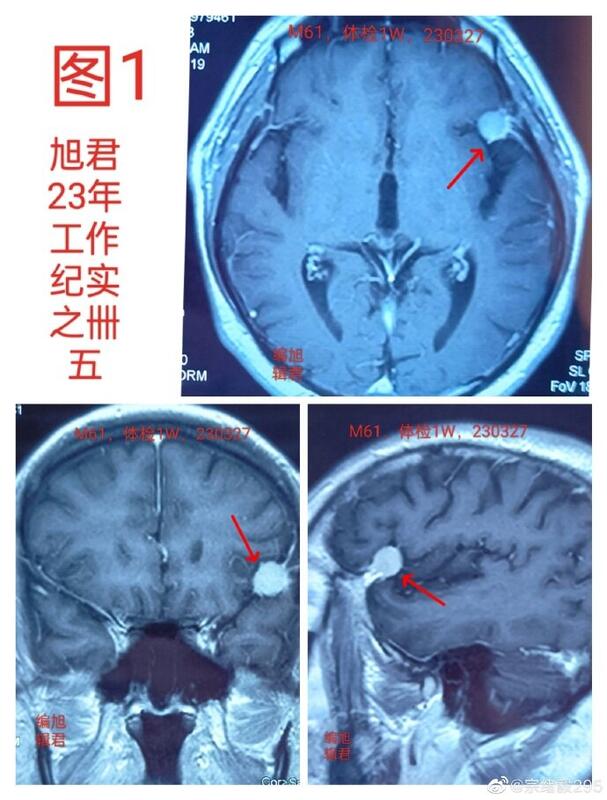

图1:某患者61岁,体检发现小脑膜瘤,无任何不适。

图-1